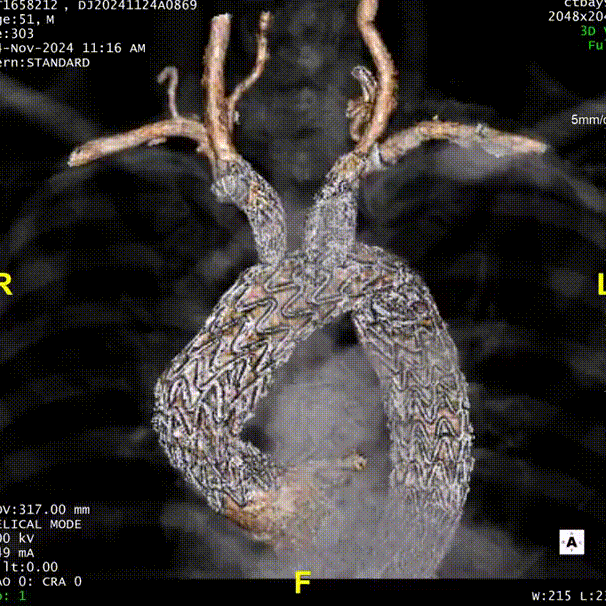

患者术后复查,CTA显示支架形态良好,弓上分支血流通畅。

gore医疗怎么样「胸有乾坤」强弓硬弩 一蹴而就——CTAG弓上三开窗治疗主动脉夹层病例报道_https://www.jmylbn.com_新闻资讯_第18张

术后复查CTA

gore医疗怎么样「胸有乾坤」强弓硬弩 一蹴而就——CTAG弓上三开窗治疗主动脉夹层病例报道_https://www.jmylbn.com_新闻资讯_第19张

术后3D重建